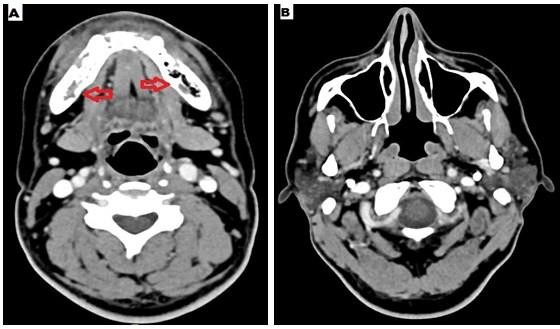

Case 1: He was a 39 year old male presented with left jaw pain for two months. He was diagnosed with Covid-19 pneumonia and required oxygen with dexamethasone at a dose of 6mg twice a day followed by once a day for total 14 days eight months ago. Due to his jaw pain he consulted dentist before coming to our instituition and underwent left 3rd molar extraction. Following the procedure his symptoms did not improve rather worsened. Pain and swelling increased gradually and there was oozing from the tooth extraction site. He did not have any sinus symptoms and underwent CT scan which revealed left mandibular osteomyelitis (Figure 1). No sinus tenderness was present and sinus endoscopy showed normal mucosa. HbA1C was 9.2%. Debridement of left mandible with extraction of corresponding molars was done. Histopathology from the debrided tissue showed aseptate, broad fungal hyphae with obtuse angle branching with bony and angioinvasion characteristic of mucorales (Figure 2). However fungal culture was negative. He was treated with 2 weeks injection amphotericin - b lipid emulsion which he tolerated well without any toxicity.

Figure 1 A- CT mandible - left mandibular osteomyelitis with expansion of the cortex, B- CT paranasal sinuses – normal.